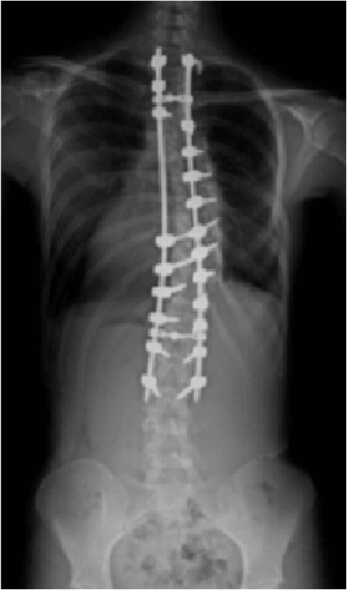

脊柱変形

思春期の女の子に多い特発性側弯症や、成人・高齢者の後側弯症(腰曲がり)などの脊柱変形に対し、椎弓根スクリューを使用した矯正術を行っており、脊椎脊髄病学会認定指導医が厳密な手術適応のもとに、最先端の装置、技術を導入し、安全かつ確実に実施しています。

25歳女性(特発性側弯症:遺残例)

手術前

手術後